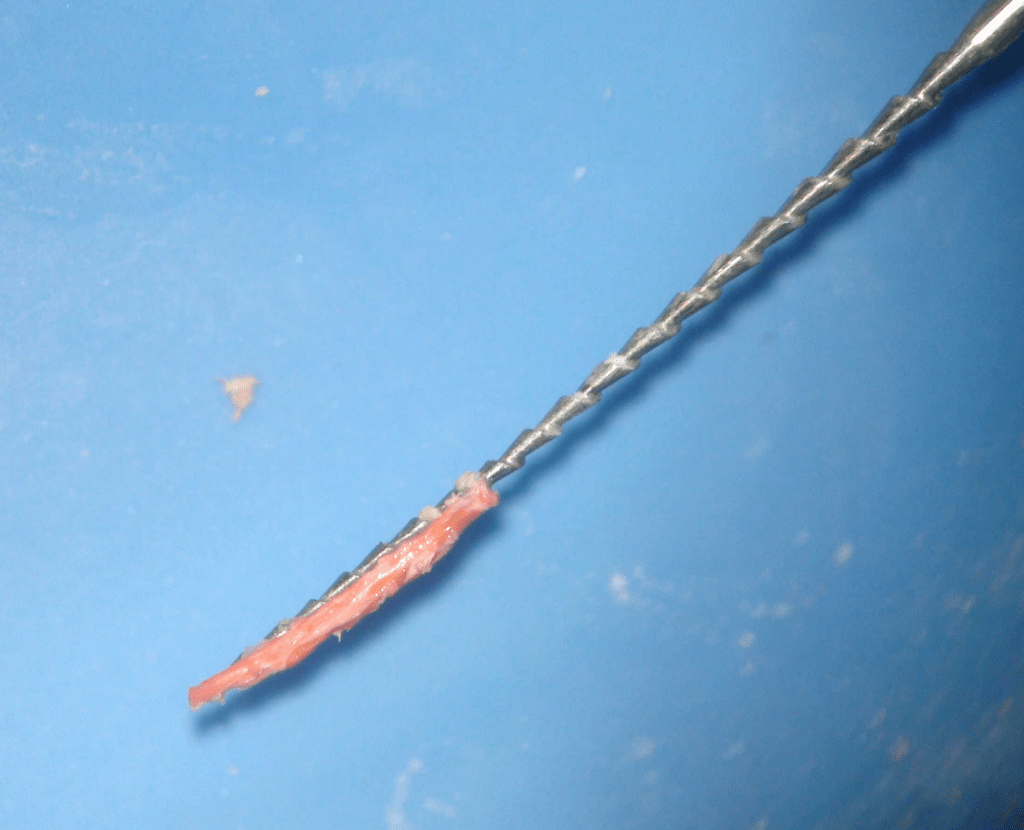

Pulpotomía biodentine + reco preendio